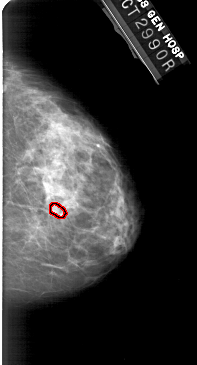

FILE: A_1949_1.RIGHT_MLO.OVERLAY

TOTAL_ABNORMALITIES 1

ABNORMALITY 1

LESION_TYPE CALCIFICATION TYPE PLEOMORPHIC DISTRIBUTION CLUSTERED

ASSESSMENT 4

SUBTLETY 3

PATHOLOGY BENIGN

TOTAL_OUTLINES 1

BOUNDARY